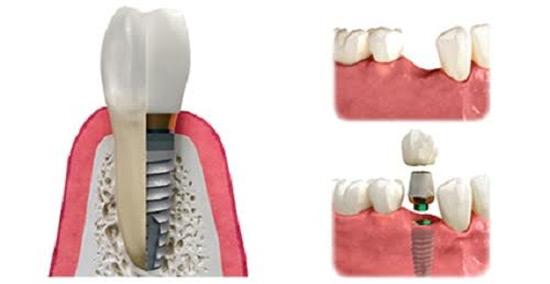

Cấy ghép Implant lên răng tức thì nhanh chóng là cách mà bác sĩ sẽ sử dụng loại Implant ETK Active để tiến hành cấy ghép vào bên trong xương hàm nơi những chiếc răng bị mất với nhiệm vụ như một chân răng thật.

Khi trụ Implant này tích hợp chặt chẽ với xương hàm thì bác sĩ sẽ thực hiện lên răng sứ tức thì trên trụ Implant tạo thành một chiếc răng hoàn chỉnh giống hệt răng thật. Thời gian thực hiện cho toàn bộ quá trình cấy ghép Implant ETK Active chỉ mất 1 - 3 tuần là hoàn thành, rút ngắn rất nhiều thời gian so với các loại Implant cũ trước đây.

Bước 5: Phục hình răng sứ trên Implant

Sau khi cấy ghép Implant xong thì sau 1 - 3 tuần là bệnh nhân có thể thực hiện phục hình răng sứ trên Implant để tạo thành một chiếc răng giả hoàn chỉnh.

Kết quả sau khi phục hình răng sứ trên Implant ETK Active